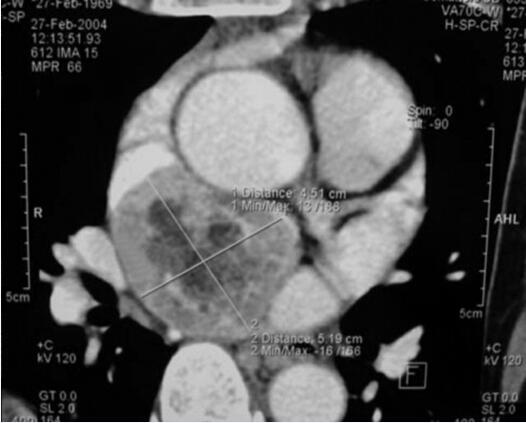

腹部CT未见异常;UCG提示左室肥厚,舒张功能降低;MIBG(-);奥曲肽显像示双侧颈动脉及纵隔右前方异常放射性浓聚区,考虑多发异位嗜铬细胞瘤;心脏增强CT显示心脏后方肿瘤(图31-4);颈部增强CT见左、右侧颈动脉分叉处直径5cm、3cm肿瘤(图31-5);冠脉造影回旋支近段发出心房支向瘤体供血,造影中有两次血压突然增高,最高达200/125mmHg,经硝普钠等治疗后可控制正常。

图31-4 心脏增强CT示心脏后方肿瘤